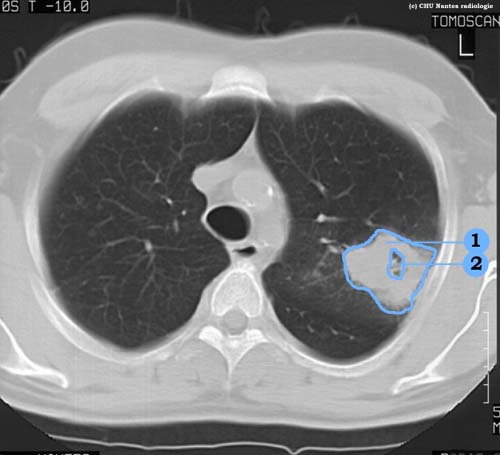

Lésions cavitaires

coupe TDM en fenêtre parenchymateuse

1 . masse solide à bords épais du lobe supérieur

2 .  centre excavé (caverne)